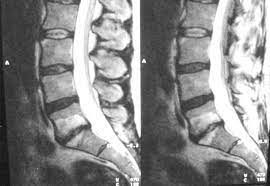

Auf dem MRT erkennt man ein deutliches Narbengewebe. Narbengewebe nach Bandscheiben-OP Zunächst sollte geklärt werden ob die Beschwerden tatsächlich vom Narbengewebe kommen. Habe vor einem Jahr Bandscheiben OP bei L45 mit anschließend 6 Wochen nicht sitzen und darauf 5 Wochen Reha gehabtDie eigentl.

Es kann vorkommen dass nach einer Wirbelsäulen OP Narbengewebe die Nerven bedrängt und das zu erneuten Schmerzen führt. Diese treten typischerweise einige Zeit nach der Operation auf Narben brauchen Zeit sich zu bilden.